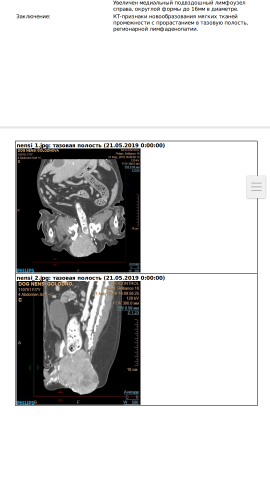

В начале, начала плохо ходить в туалет, по большому, значения не предала, думала от еды, зная как её кормят. Но в последнее время около хвостика, образовалась шишка. Как не заметила, не понимаю, корю и веню только себя. Поехали в вет клинику, сдали анализы крови, КТ, говорят, что это раковая опухоль, лечению не подлежит. Даже если сделать операцию, вырастит через несколько месяцев.